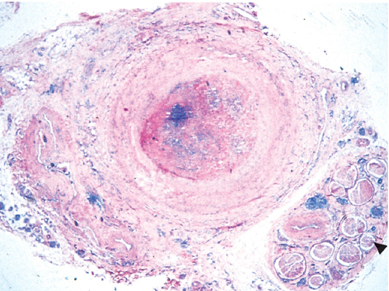

coronary artery section in pt with familial hypercholesterolemia. what’s in it?

platelets and RBCs + fibrin = thrombus (at an early age)